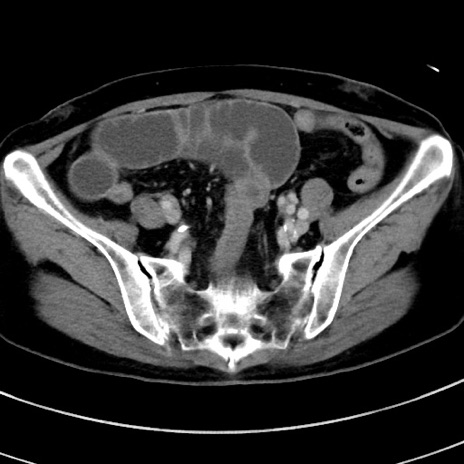

症例9(横断像)

【症例】 60歳代女性

【主訴】むかつき、みぞおちの痛み

【現病歴】3日前よりむかつきがあり、食事がとれない。

【既往歴】糖尿病

【身体所見】発熱なし、心窩部圧痛軽度あるも、腹膜刺激症状なし。

【データ】WBC 7400、CRP 1.92